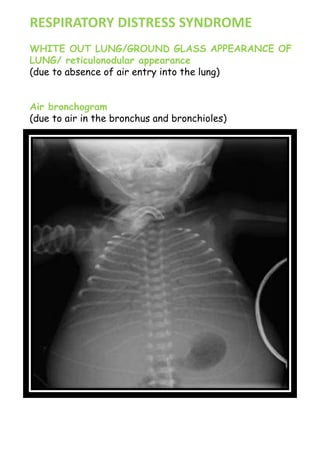

RESPIRATORY DISTRESS SYNDROME

WHITE OUT LUNG/GROUND GLASS APPEARANCE OF

LUNG/ reticulonodular appearance

(due to absence of air entry into the lung)

Air bronchogram

(due to air in the bronchus and bronchioles)

Bilateral involvement

Preterm

Alveoli are not

expanded, air is entering

all the airways  even

the smallest bronchioles